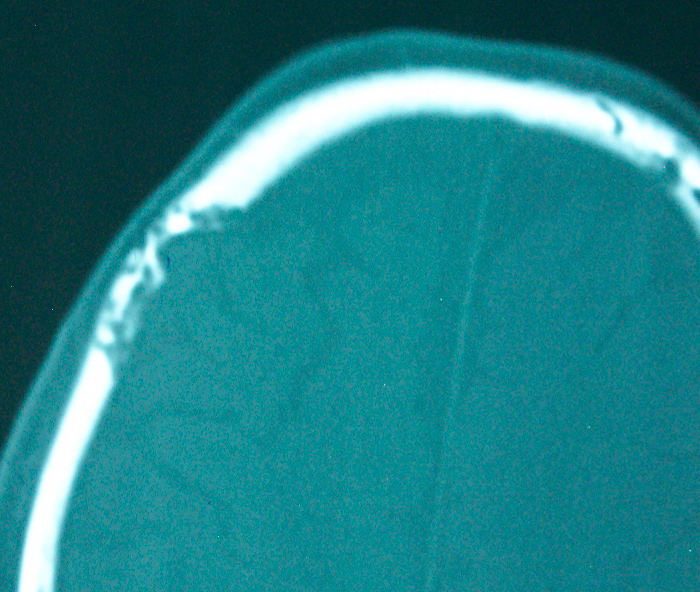

以下是引用余辉在2009-4-15 20:49:00的发言:[br]右侧病灶发生于冠状缝区,但额骨左侧鳞也有病灶,病灶区脑沟裂增宽(有脑萎缩征像,把这个征像放在颅骨病变一起考虑可能有点牵强),是否可能是板障血管畸形所致谢?抑或是嗜酸性肉芽肿或蛛网膜粒压迹那类东西?

以下是引用whzht在2009-4-15 20:57:00的发言:[br]1、额骨改变,考虑蛛网膜粒压迹;[br]2、脑萎缩。